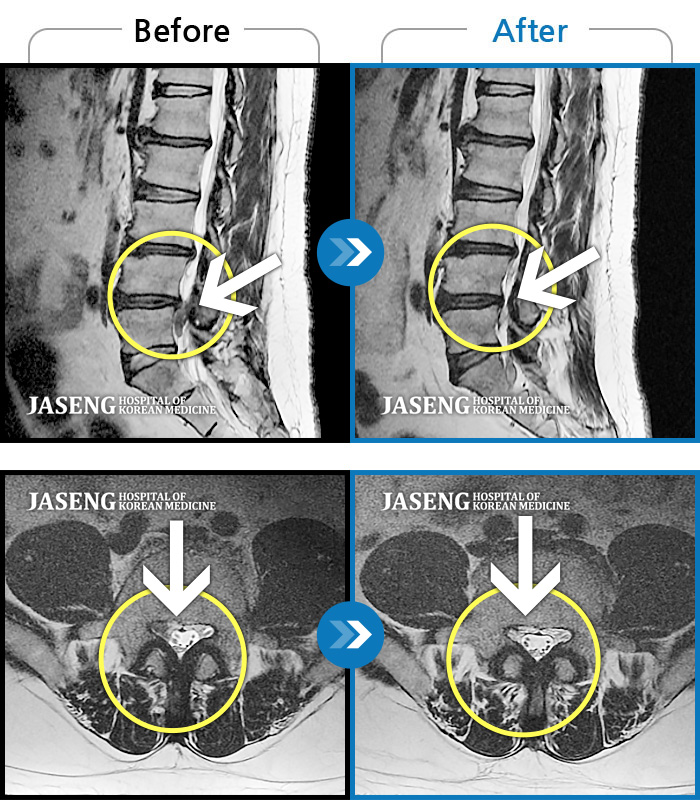

MRI 치료사례

하요추부, 우측 둔부 통증 및 우측 하지 비증